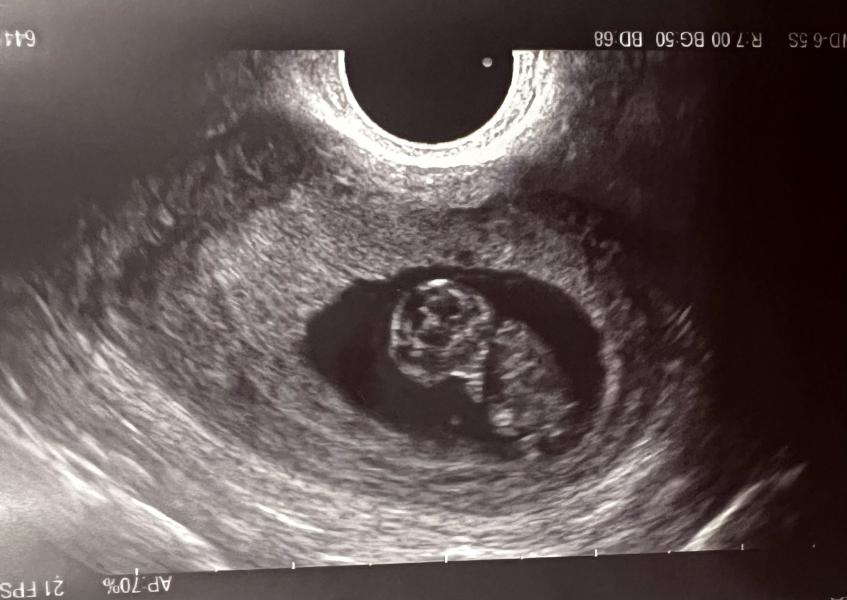

Были сегодня на УЗИ. Акушерский срок 9 недель и 3 дня. А малыш опережает на неделю, врач поставил срок 10 недель☺️. Ото мне и плохо очень видимо, слишком быстро растет😄! На УЗИ уже видно полноценного человечка с ручками и ножками. И даже пальчики разглядели) это чудо 🥰

Я всегда мечтала о девочке, но муж говорит это мальчик, раз так быстро развивается 😂ЧТО ДУМАЕТЕ ПО ЭТОМУ ПОВОДУ?